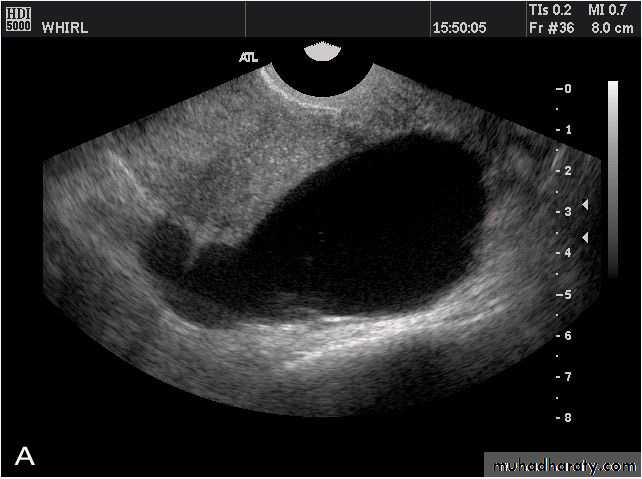

Hemorrhagic ovarian cysts:

Hemorrhagic cyst of ovary resulting from Ovulation induction

This young nulliparous female patient undwerwent ultrasonography following ovulation induction. The right ovary shows a typical hemorrhagic cyst formed from the corpus luteum. The first image (top row- left) is a transabdominal ultrasound image showing fine fibrinous strands within the cystic mass in the right ovary. Transvaginal ultrasound and color Doppler images confirm these findings. The uterus shows typical secretory changes in the endometrium suggesting post ovulatory phase.